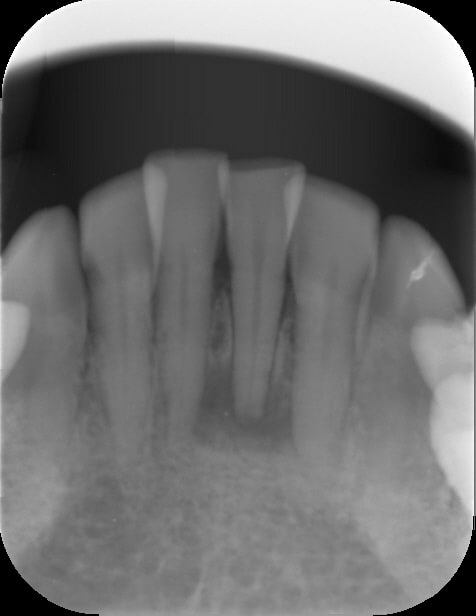

oh bin mince alors ... what a surprise ! qu'est ce qu'on voit à la radio...

encore une allumée qui a des sensibilités au froid sur une dent nécrosée. :)